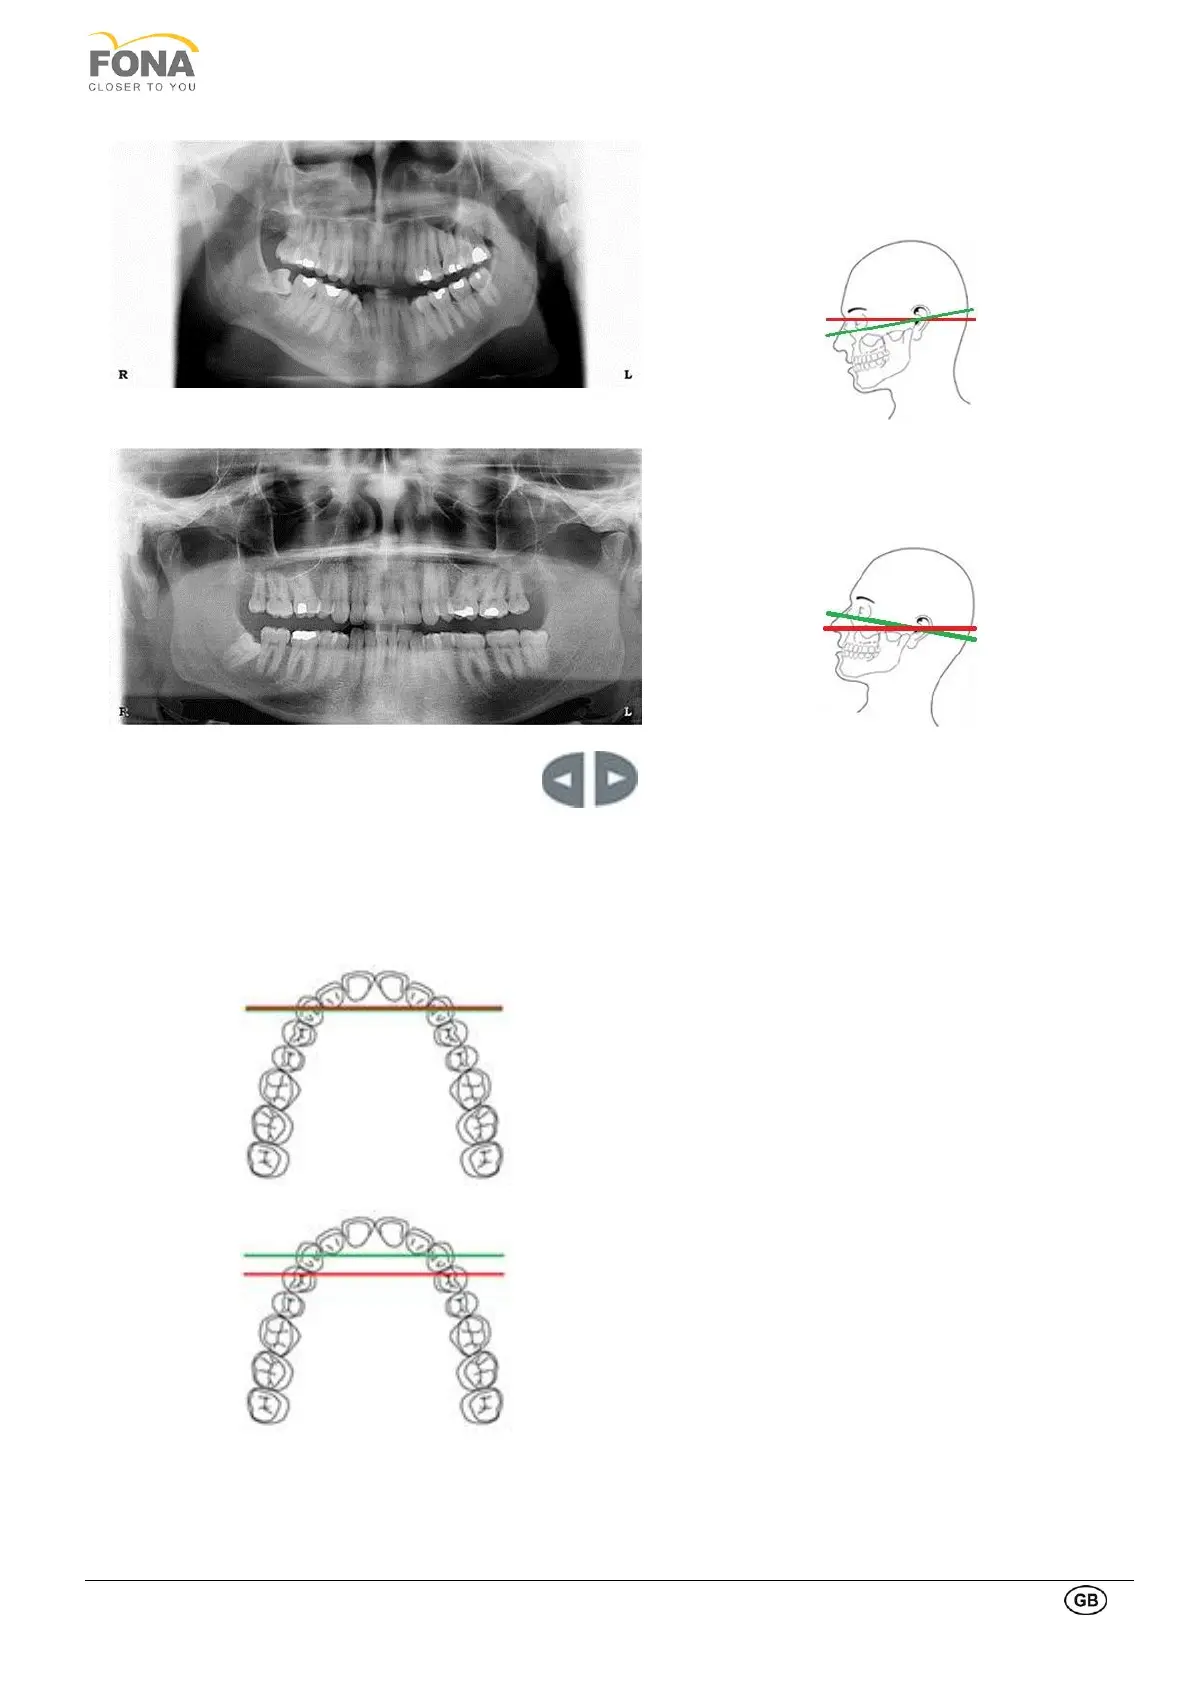

Wrong position:

Frankfurt plane is NOT horizontal

The head is tilted forward thus resulting in a V

shaped dental arch on the X-Ray image.

The head is tilted backward, thus resulting in a flat

dental arch on the X-Ray image.